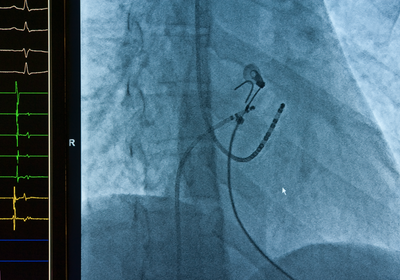

Implantable cardiac monitors allow for continuous heart monitoring and are a major advancement in detecting arrhythmias. These miniature devices are implanted just under the skin in a minimally invasive outpatient procedure. They can detect and record arrhythmias continuously for up to three years, allowing for the detection and diagnosis of conditions that may not show up during standard office-based ECG or Holter monitoring tests. The data is wirelessly transmitted to a secure database where it can be monitored remotely by physicians. This provides a significant advantage over external looping monitors by allowing for detection of infrequent arrhythmias.